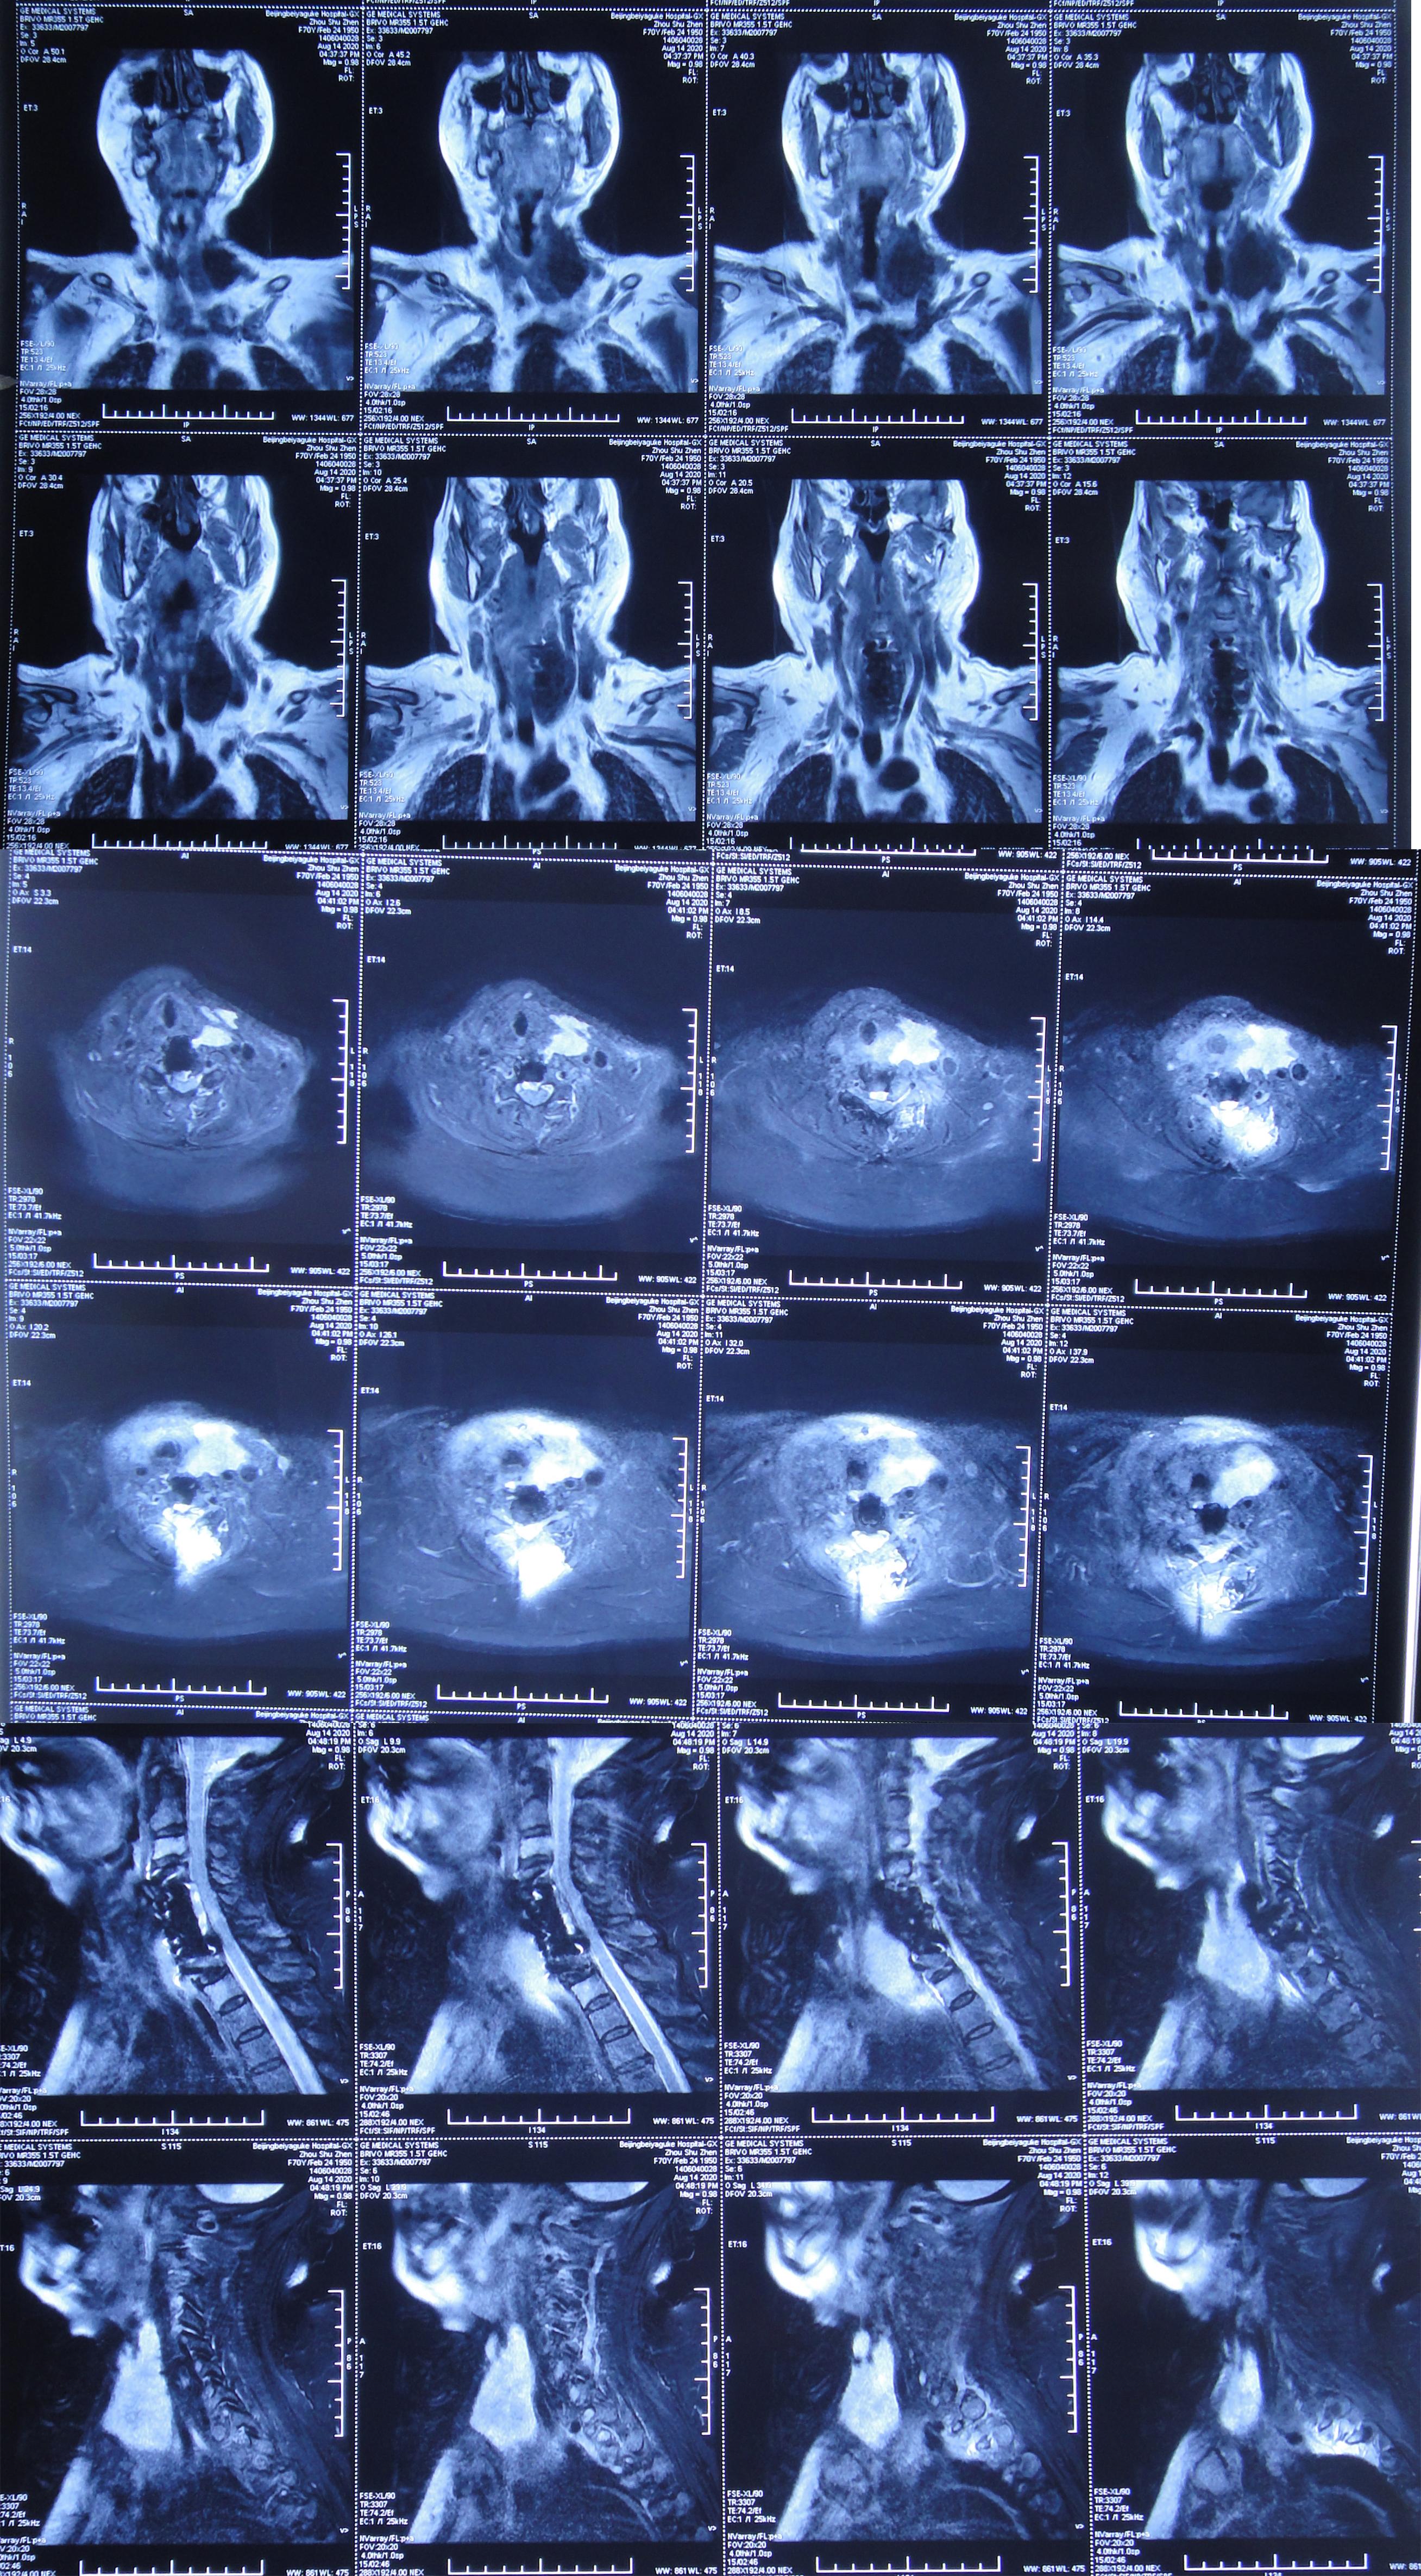

2020年8月13日(即第二次颈椎病术后第8天)患者开始出现颈部肿胀,床旁B超检查发现颈部切口深部积液,超声引导下穿刺抽出约87ml淡黄色透明液体,同时积液送细菌培养。2020年8月14日(即第二次颈椎病术后第9天)再次在床旁B超引导下穿刺抽液,抽出约90ml淡黄色透明液体,并加压包扎。复查颈部MR示术区皮下大量包裹性积液,考虑脑脊液漏( 图-8 )。

图-8: 2020年8月14日颈部MR

2020年9月2日(入脑脊液科次日,即颈椎脑脊液漏修补术后第6天,即第二次颈椎病术后第25天)复查颈部MR示术区皮下深部仍有包裹性积液( 图-10 )。

图-10: 2020年9月2日颈部MR